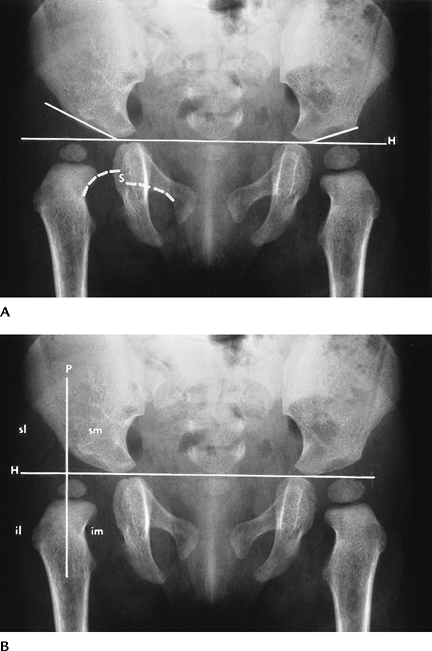

Radiographs (AP and frog-leg

dysplastic hips (Fig. 4-48A). Shenton line

the normal hip. The arc is interrupted in dysplastic hips (Fig. 4-48A).

Features become more obvious with age. Perkin line is perpendicular to

Hilgenreiner line (line through triradiate cartilage). This divides the

hip into quadrants. The femoral head or medial metaphyseal beak should

lie in the inferior medial quadrant (Fig. 4-48B). -

FIGURE 4-48 AP radiographs (A,B) demonstrating developmental dysplasia on the right. The acetabular angle (line

along acetabulum to Hilgenreiner line [H]) is increased and the hip is displaced superolaterally with interruption of Shenton line (S) (broken white lines). The femoral head should lie in the inferomedial (im) quadrant. Four quadrants (im, inferomedial; il, inferolateral; sl, superolateral; sm, superomedial) are formed by a line (Perkins line) at the acetabular margin perpendicular to Hilgenreiner line. The femoral head is out of the im quadrant in (B). |